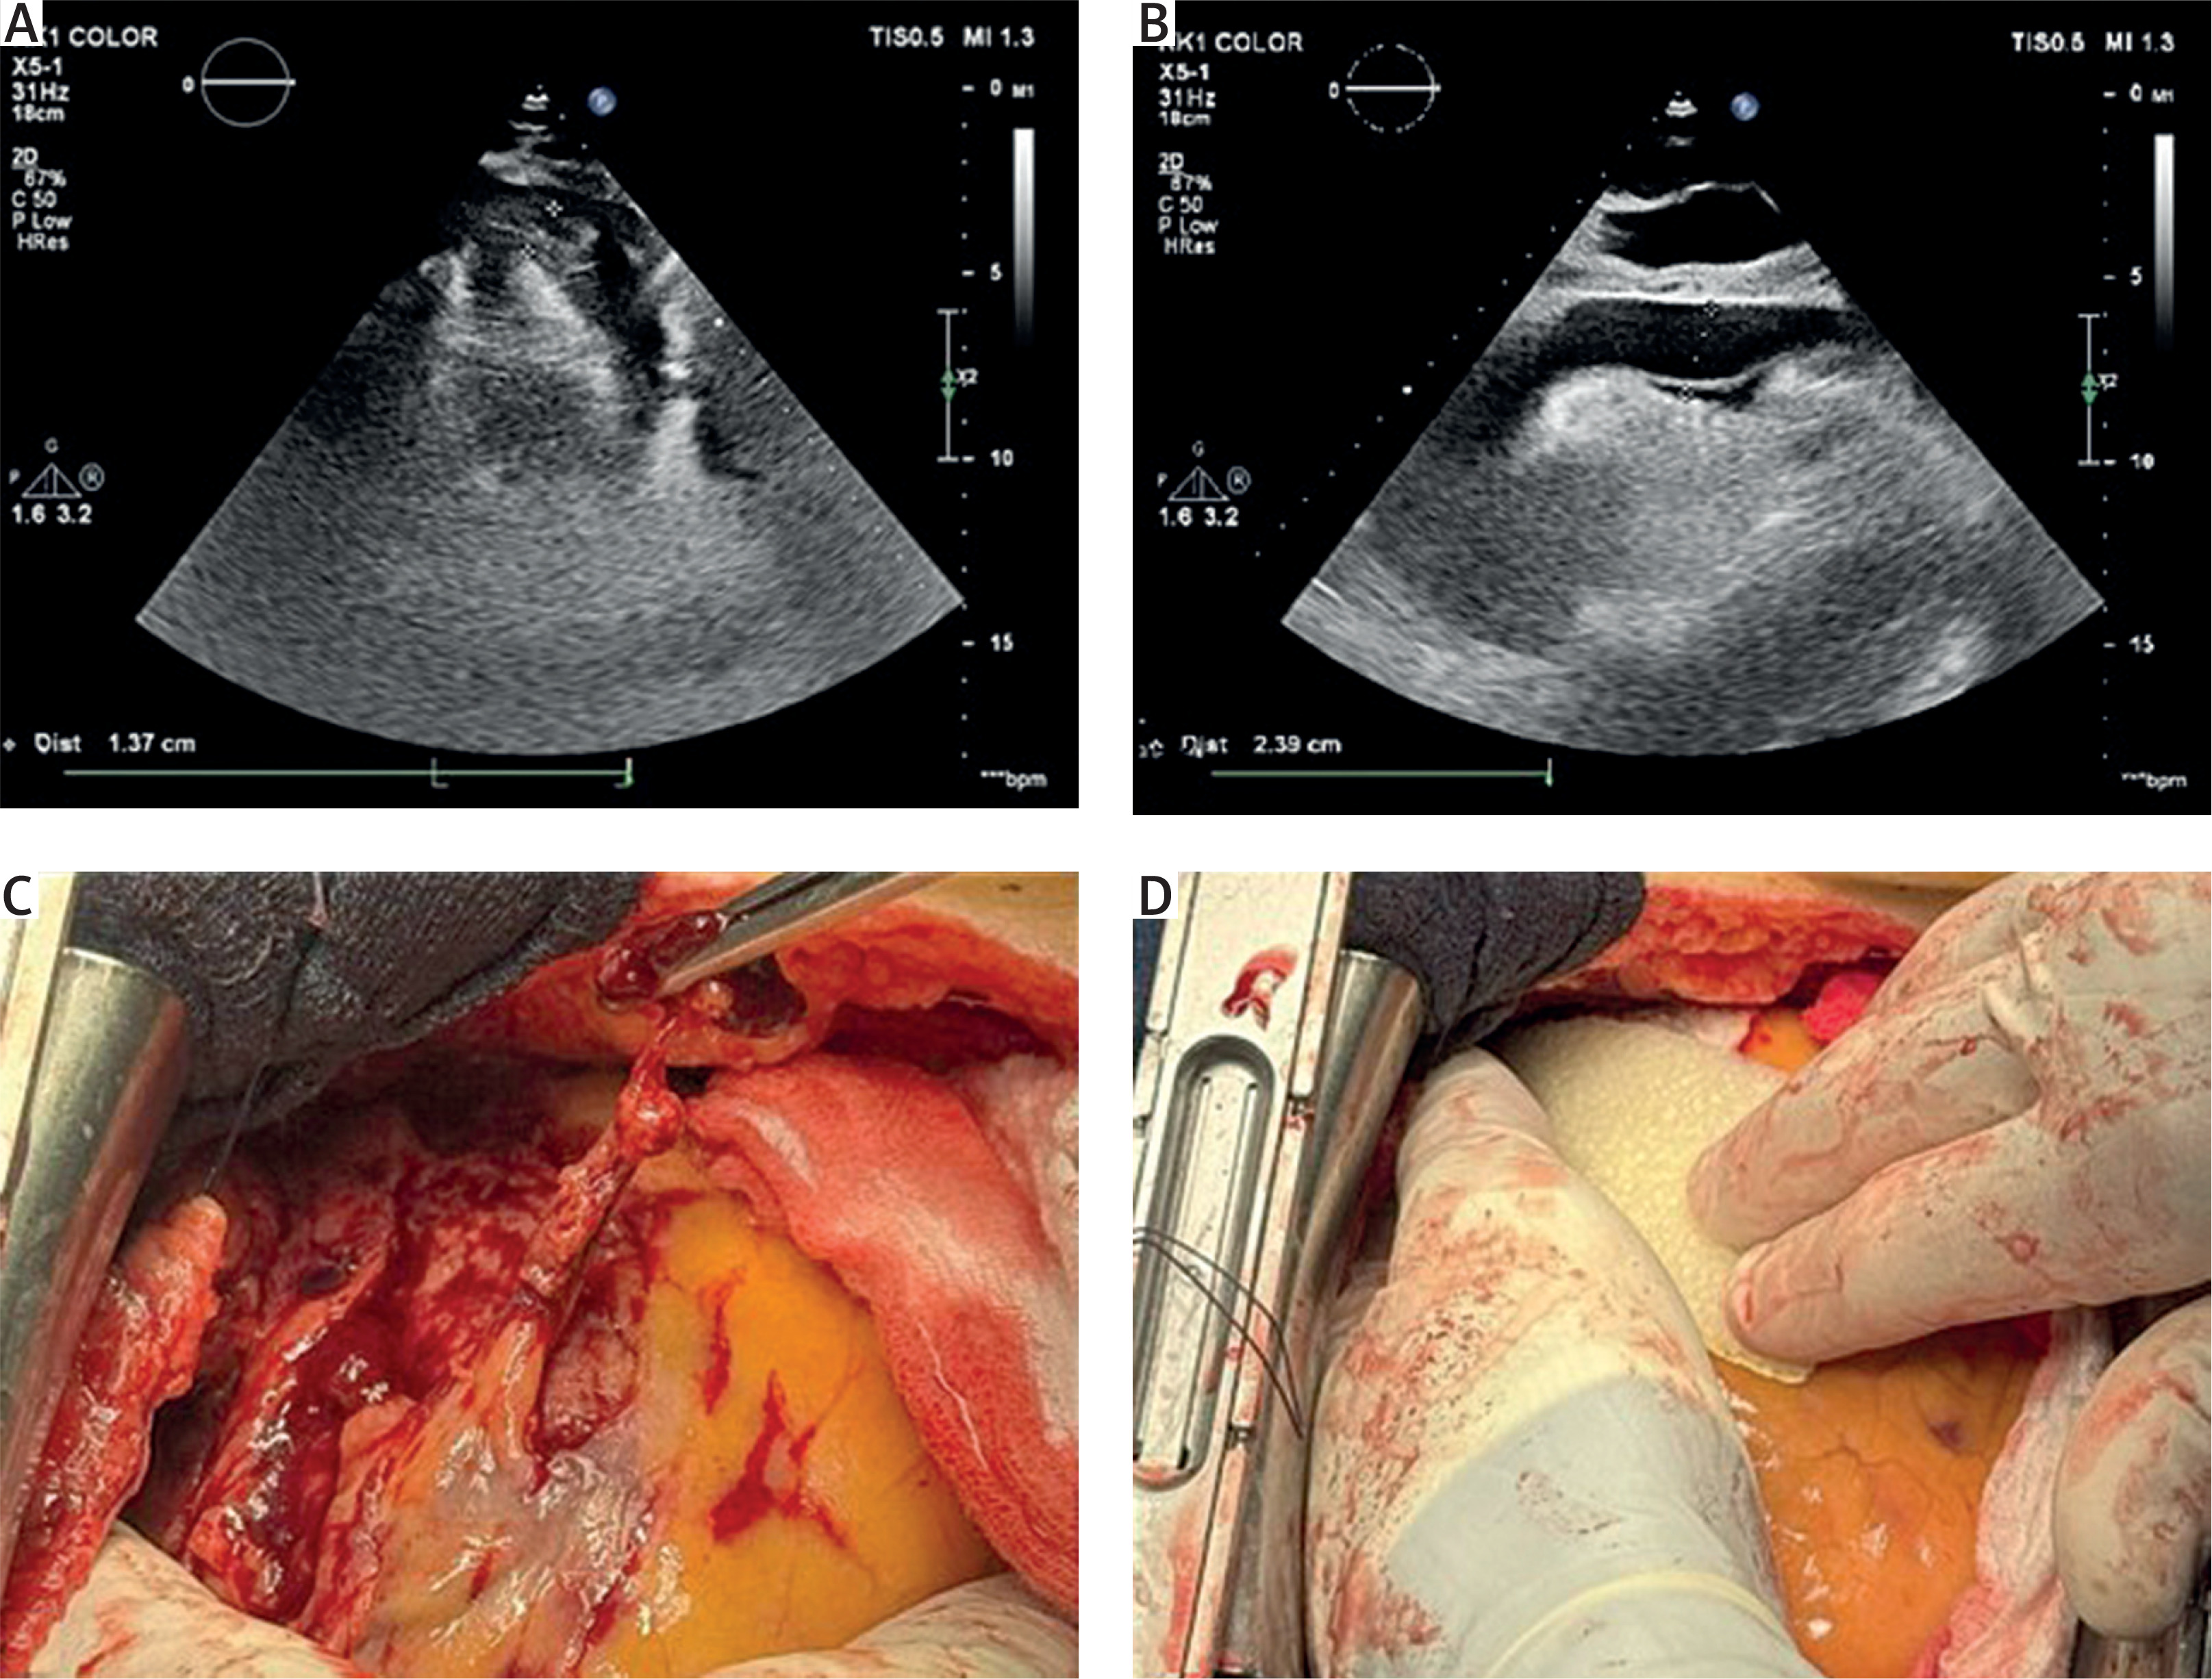

A 78-year-old male patient with chronic heart failure, hypertension, permanent atrial fibrillation (AF), previous stroke, history of gastrointestinal bleeding and prior percutaneous coronary intervention (PTCA) with stent implantation was admitted with blunt thoracic trauma the day after a bicycle accident. Due to the presence of coronary stents and permanent AF, the patient was maintained on combined antiplatelet and anticoagulant therapy. Upon admission, the patient was unconscious and mechanically ventilated, exhibited hemodynamic instability, and was on high doses of inotropic drugs. Trauma computed tomography revealed heterogeneously dense pericardial fluid, intracerebral and subdural hemorrhages, which did not require neurosurgical intervention, facial fractures, suspected cervical spine injury, and free fluid within the abdominal cavity. Transthoracic echocardiography identified systolic collapse of the free wall of the right ventricle, with a pericardial effusion measuring 24 mm anterior to the RV with an organized clot measuring 15 mm (Figures 1 A, B). In light of the patient’s numerous clinical comorbidities and the concomitant administration of antiplatelet and anticoagulant therapies, it was deemed necessary to proceed with a minimally invasive pericardiocentesis performed via a pigtail catheter under echocardiographic guidance. Attempted percutaneous drainage resulted in iatrogenic puncture of the right ventricular free wall, prompting urgent conversion to sternotomy. During the procedure, it was confirmed that the pigtail catheter was placed in the right ventricle. The catheter was carefully withdrawn, and the insertion site in the diaphragmatic surface of the right ventricle was secured with 4.0-sutures and Teflon patches. Intraoperatively, an epicardial flap tear (2 × 3 cm) of the anterior wall of the right ventricle was identified. In addition, multiple epicardial-pericardial adhesions divided the pericardial sac into compartments with varying amounts of clots (Figure 1 C). Hemostasis was successfully achieved with application of a TachoSil patch (Baxter) (Figure 1 D). Due to thrombocytopenia (platelet count of 72,000/μl), elevated INR level (1.7) and antiplatelet and anticoagulant therapy, delayed chest closure was performed. The chest was finally closed the next day. Postoperatively, the patient required mechanical ventilation, high-dose vasoactive support, dialysis, and anticonvulsant medication. Despite maximal intensive care treatment, the patient progressed to refractory multiorgan failure. Unfortunately, on the sixth day after the operation the patient died. Blunt cardiac trauma (BCT) is an uncommon but potentially fatal consequence of chest injury, with reported incidence less than 10% in all trauma admissions although it is responsible for approximately 25% of traumatic deaths [5]. Among its severe complications, cardiac tamponade though rare requires urgent identification and management. In this case, a 78-year-old man with multiple comorbidities sustained blunt thoracic trauma complicated by pericardial tamponade. Pre-existing pericardial adhesions likely resulting from prior cardiac history facilitated tamponade development. The patient’s chronic anticoagulant and antiplatelet therapy for AF and coronary artery disease impaired physiological hemostasis, contributing to ongoing hemorrhage and complicating conservative management of the pericardial effusion. This illustrates the difficult balance between bleeding risk and thromboembolic protection in cardiovascular patients [6]. Transthoracic echocardiography revealed localized tamponade with systolic collapse of the right ventricular free wall, a dynamic finding linked to uneven pericardial pressure from organized clot and adhesions. Faced with acute hemodynamic instability and high hemorrhagic risk, an echocardiography-guided pericardiocentesis was performed. Although image-guided pericardiocentesis is considered safe in trauma settings, in this patient it led to iatrogenic ventricular laceration, necessitating urgent conversion to open sternotomy for definitive repair. This case underscores several key clinical insights. First, cardiac tamponade is a life-threatening condition that requires immediate intervention, and neither comorbidity nor coagulopathy should be viewed as a complete contraindication to lifesaving procedures. Second, even echocardiography-guided pericardiocentesis may be unsafe or ineffective when loculated effusions, adhesions, or organized clots are present. Lastly, structural vulnerability such as surgical adhesions combined with pharmacological anticoagulation can convert seemingly minor blunt trauma into a catastrophic event, highlighting the importance of tailored procedural planning and preparedness to escalate to surgical intervention.